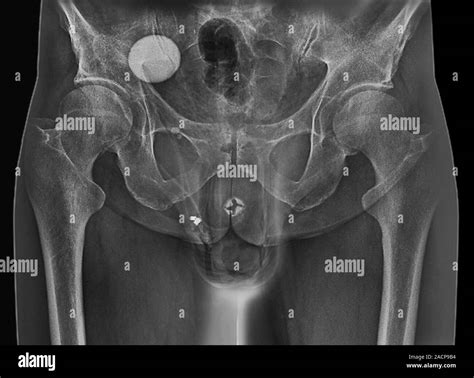

An Artificial Urethral Sphincter is a surgically implanted device designed to mimic the function of the natural sphincter muscle, which normally keeps the urethra closed to prevent urine leakage. When this natural muscle is damaged or weak, the AUS takes over the responsibility of controlling the flow of urine. The device is entirely contained within the body, making it discreet and effective for long-term use.

The system typically consists of three interconnected components:

• The Cuff: A circular balloon placed around the urethra that inflates to keep the urethra closed.

• The Pump: A small control mechanism placed in the scrotum (for men) or labia (for women) that allows the patient to manually deflate the cuff when they need to urinate.

• The Balloon (Pressure-Regulating Reservoir): A reservoir implanted in the abdomen that regulates the pressure within the system to ensure the cuff stays closed yet comfortable.

• artificial urethral sphincter radiology